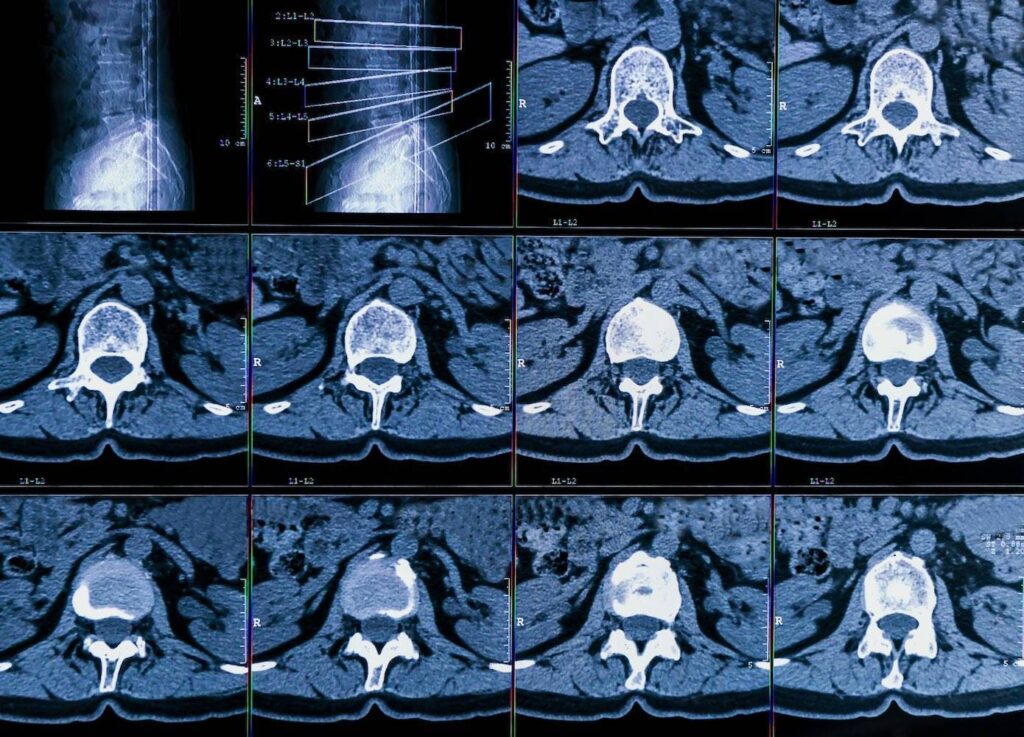

Nach der körperlichen Untersuchung kann der Arzt die Diagnose mit Hilfe von bildgebenden Verfahren wie Röntgenaufnahmen, CT-Scans oder MRT-Scans bestätigen. Es gibt auch Fälle, in denen ein Arzt einen Nervenleitungstest oder eine Elektromyographie durchführen kann, um zu prüfen, ob die Nervenwurzel geschädigt ist. Die häufigste bildgebende Untersuchung zur Diagnose der Erkrankung ist die MRT, die detaillierte Bilder der Weichteile im unteren Rücken liefert.

Die MRT-Untersuchung kann mit einem in die Blutbahn injizierten Kontrastmittel durchgeführt werden, aber das ist nicht immer der Fall. Mit dem Test kann festgestellt werden, welche Bandscheibe betroffen ist, wenn es eine Nervenkompression gibt. Mit dem MRT-Scan können auch Rückenmarkstumore, Abszesse und knöcherne Überwucherungen erkannt werden.